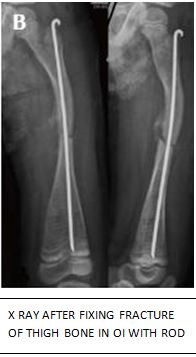

* Fixing fractures when needed- most fractures in young children can be treated with plaster casts, as children grow older fractures which need surgery to fix them can occur.

* Correcting bowing of bones- When the bend in the bone is too severe for the child to walk or work it needs correction by surgery. In this procedure bent bones are cut to straighten them and then fixed by putting metal rods inside them.

* To prevent frequent fractures by strengthening them- This also involves placing metal rods

within bones- these are left in place for long.

Surgical fixation with metallic plates and screws is not done in OI because it tends to fail due the defective bone. Instead, metallic rods placed inside bones are used commonly. These rods need to be changed when bones bearing them outgrow the rods. An alternate option is to use growing rods which have recently come up in the western world and are costly.